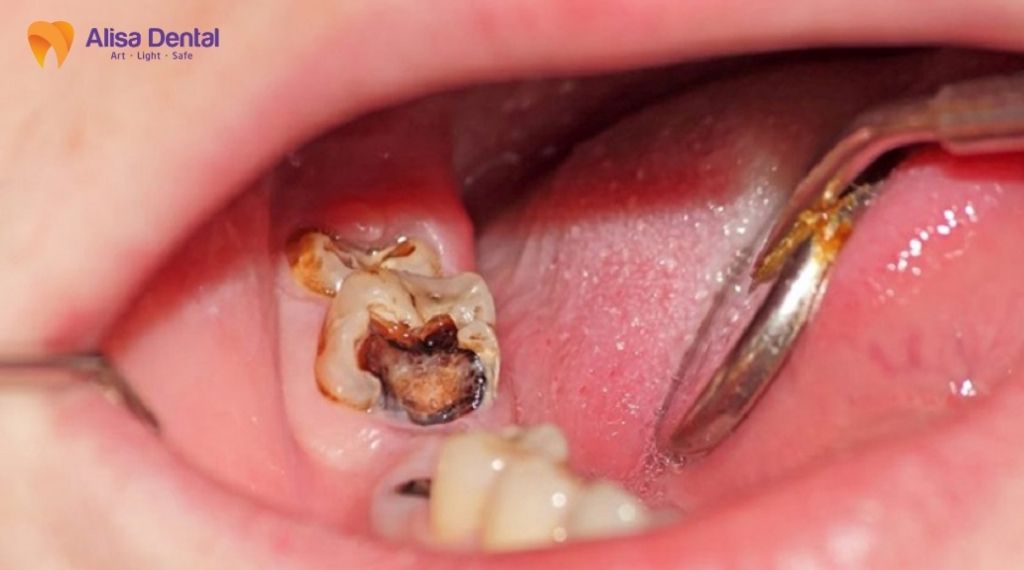

Trường hợp 1: Sâu răng nặng ăn vào tủy

Đây là nguyên nhân phổ biến nhất khiến bệnh nhân buộc phải tìm đến phương pháp điều trị tủy. Khi vi khuẩn tấn công, chúng sẽ phá hủy lớp men răng cứng bên ngoài, sau đó ăn mòn lớp ngà răng và cuối cùng xâm nhập vào buồng tủy – nơi chứa dây thần kinh và mạch máu.

Ở giai đoạn này, lỗ sâu thường rất lớn, có thể nhìn thấy bằng mắt thường (màu nâu hoặc đen). Vi khuẩn sinh sôi trong buồng tủy gây ra áp lực lớn, dẫn đến tình trạng viêm tủy không hồi phục. Bệnh nhân sẽ cảm thấy những cơn đau nhức dữ dội, đau buốt tận óc, đặc biệt cơn đau thường xuất hiện tự phát vào ban đêm khiến mất ngủ. Lúc này, việc trám răng thông thường không còn tác dụng, bác sĩ bắt buộc phải lấy sạch phần tủy đã nhiễm trùng để cứu giữ chiếc răng thật.